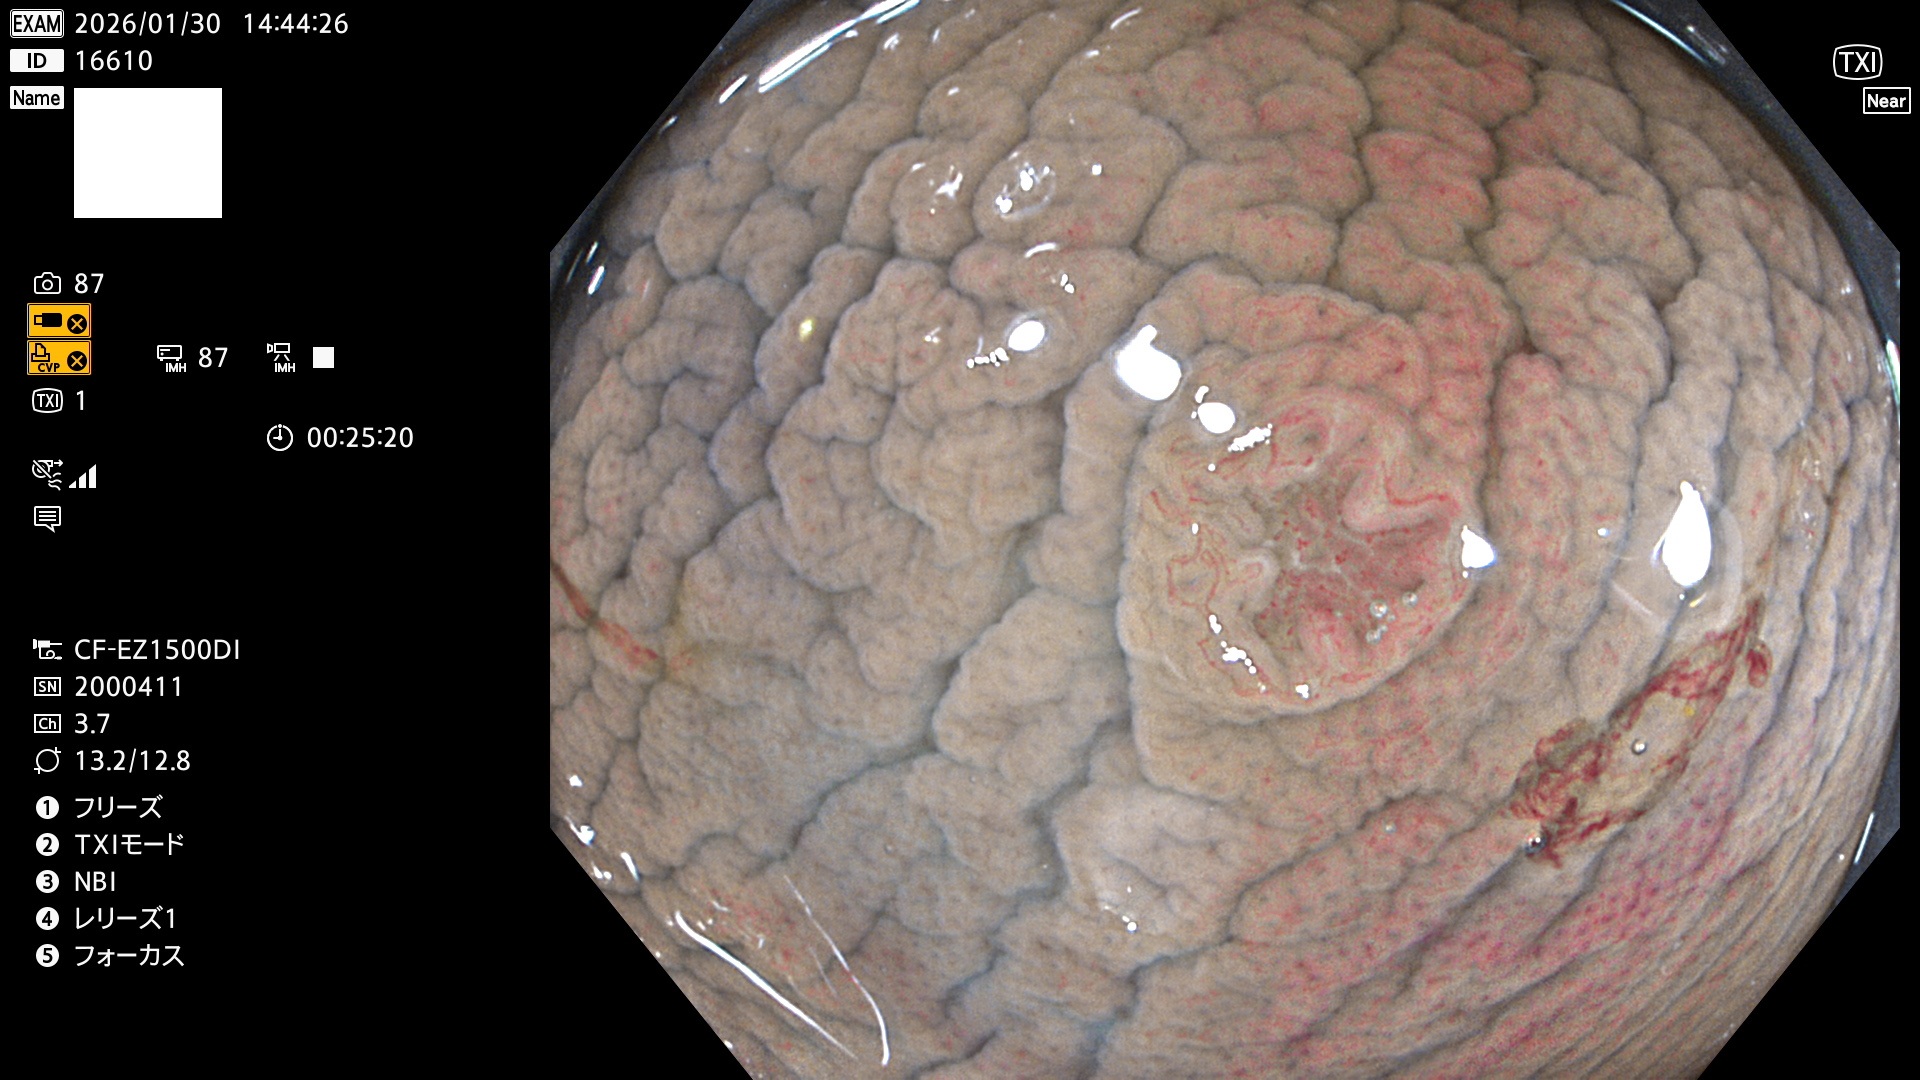

完全に平坦な物をUb、陥凹している物をUcと呼びます。Ubは認識が困難で、Ucはびらん(炎症)と紛らわしいために見落とされやすく、「内視鏡後・大腸癌」の原因になります。

専門的)Uc=De Novo癌? 内視鏡の解像度が低かった時代、このような説もありました。しかし今日の高精度内視鏡では良性の微小なUc型腺腫(APC遺伝子異常の腺腫)が日常的に見つかります。Ucこそが多段階発癌(Adenoma-Carcinoma Sequence)のMain Routeです。

毎週の検査(木・金・土・日)に発見されたUbとUc型・腺腫を、その週の日曜の夜にUPし1週間、提示します。

写真公開の目的は「透明性・信憑性の担保」ですが、公開を希望されない方はメールで御連絡下さい。直ちに削除いたします。

2026年1月29日〜2月1日の4日間(40件)10個 (Uc_ADR=10個/40人=25%)